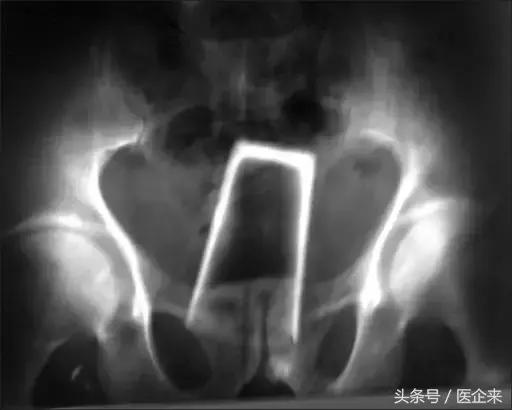

8. 啤酒瓶,还有个铁丝钩(想用铁丝勾出来?然鹅...)